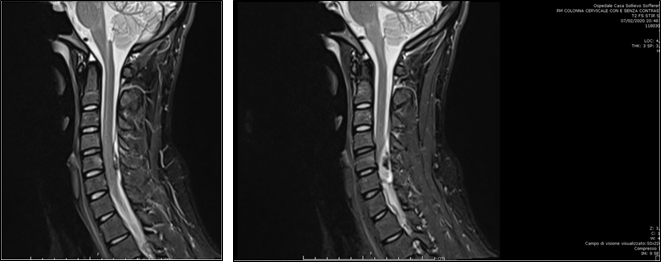

Magnetic resonance imaging (MRI) with paramagnetic contrast agent of the cervical spine (Figure 1) revealed a C4-C6 extramedullary/epidural over fluid layer occluding the posteriors perimedullary spaces. The collection was characterised by inhomogeneous signal probably linked to the presence of haemoglobin degradation products, related to the subacute evolution phase. There was an evident compressive effect on the spinal cord without signal alterations. No vessels abnormalities were found with the technique. A computed tomographic (CT) scan (Figure 2) of the cervical spine didn’t reveal fractures or other collateral findings except for the hyperdensity expressed by the extramedullary fluid collection. We leant, at the beginning, for a conservative approach keeping the patient under observation in our neurosurgery department. Three days after, the patient suddenly developed dysesthesia at the four extremities and tetraplegia with a residual capacity of slight intra rotation of the upper limbs.

Figure 1 MRI with paramagnetic contrast agent of the sagittal cervical spine revealing a C4- C6 extramedullary/epidural over fluid layer occluding the posteriors perimedullary spaces.